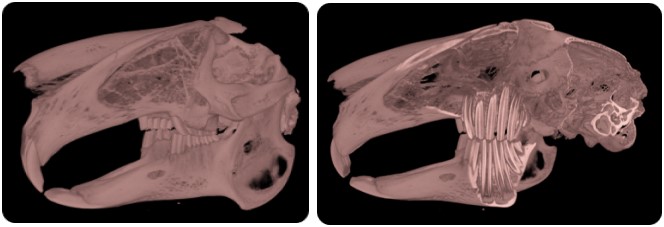

CT Features

• 52 µm resolution

• 80 (200) x 80 mm FOV single (multiple) bed positions